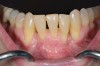

Fig 10. In this case a short vestibule was present prior to SFOT.

Figure 10

Fig 11. Suturing after SFOT procedure; note the shallow vestibule and flap tension at closure.

Figure 11

Fig 12. At 2 weeks postoperative, a flap dehiscence present on the facial was a result of the flap tension associated with the shallow vestibule.

Figure 12

Fig 13. Final outcome after SFOT; note proper alignment of teeth yet limited attached gingiva with compromised root coverage and shallow vestibule still present post-surgery.

Figure 13